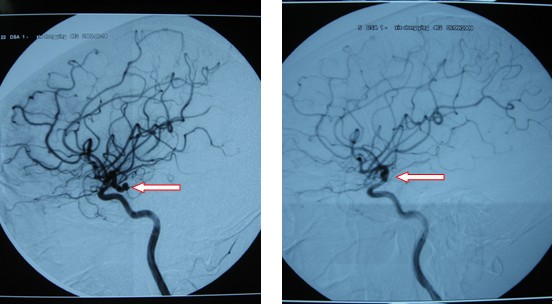

病例1:謝冬英,女,45歲,永定區人,因右眼下垂、復視3年,加重伴頭痛1周入院,入院后患者出現嚴重腦血管痙攣、導致右側肢體癱瘓。CT檢查發現自發性蛛網膜下腔出血,DSA檢查發現右側后交通動脈瘤,5×10mm大小,瘤體壓迫右側動眼神經。2009年8月23日行右側后交通動脈瘤顯微夾閉手術,術后患者逐漸康復,目前患者右側動眼神經麻痹恢復,右惻肢體肌力4級,生活基本自理。復查DSA,患者動脈瘤夾閉完全。

圖四:術前DSA發現右側后交通動脈瘤 圖五:術后DSA檢查右側后交通動脈瘤消失